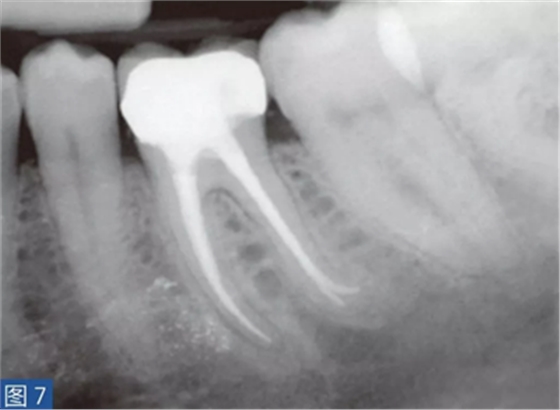

致密性骨炎(圖6 和7)是AAP 的一個(gè)變種。造成致密性骨炎的原因是,根尖周組織受到長期的持續(xù)性刺激。臨床檢查時(shí),對(duì)敏感測(cè)試、叩診和觸診可能有反應(yīng),也可能無反應(yīng)。放射學(xué)檢查,牙齒的根尖周圍存在彌漫性的致密阻射影像。

圖7:36 牙齒CO。根管再治療12 個(gè)月后。